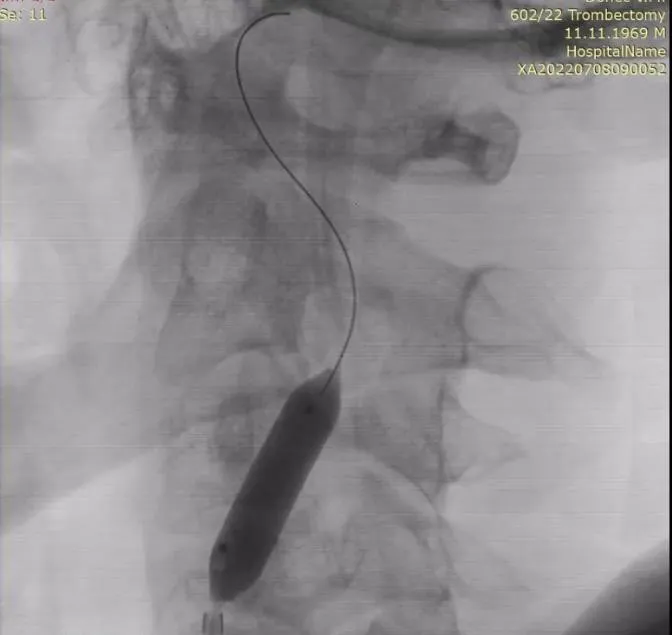

Рисунок 1. Результати нативної МСКТ голови.

При нативній МСКТ голови виявлені ознаки досить великого свіжого вогнища інфаркту в ділянці базальних гангліїв (голівка хвостатого ядра, шкарлупа та внутрішня капсула) та лобно-острівцево-скроневій області ліворуч, без ознак латерального зміщення серединних структур мозку. Оцінка за ASPECTS = 5 балів.